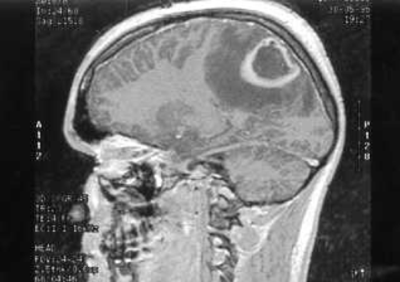

Paciente varón de 43 años. Se presenta Resonancia Magnética. ¿Cuál es su diagnóstico?

Answer

• Absceso cerebral con acumulo de pus en el parénquima cerebral.

• Metástasis de adenocarcinoma Reproducción o extensión de una enfermedad o de un tumor maligno de un epitelio glandular.

• Cerebro en condiciones normales.